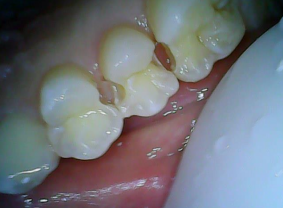

关于邻面龋坏

邻面龋是临床上非常常见的龋坏部位,指的是发生在两个牙齿之间的龋坏,龋坏新发时比较隐匿,不太容易被患者发现。针对于邻面龋,临床上最常见的原因就是由于食物嵌塞,牙缝内经常嵌塞食物残渣以及细菌,久而久之就会在该部位两侧形成龋坏的现象。

针对于邻面龋,一旦发现建议尽早到专业的口腔科进行治疗,拍摄牙片确定邻面龋,并查看范围以及深度,应用牙科的动力系统,从颌面将邻面打开去除龋坏的部位,应用成形系统将牙齿修补好,邻面龋就算治疗完成。

以下是邻面龋坏补牙过程: